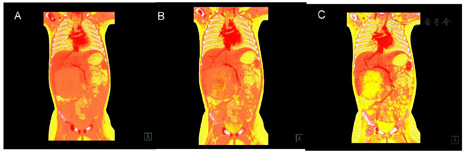

CT图像显示肝右前叶见一巨大囊实性肿物,大小约83mm×63mm×99mm,肿物以囊性成分为主,见粗细不均匀分隔,实性成分呈结节状、斑片状向囊腔内突出,增强后分隔及实性成分见轻度强化,肿物内见纤细血管影,肿块下方部分向腹腔内突出,边界清楚,内壁光滑(图1和图2)。患者随后行"剖腹探查,肝癌切除,胆囊切除,门静脉探查术",冰冻病理示:形态较符合间叶性错构瘤。石蜡切片示肝组织内可见大量疏松水肿的纤维结缔组织明显增生伴粘液样变,其内见萎缩的肝细胞岛,形态符合肝间叶性错构瘤。

DECT采用选择性光子屏蔽(SPS Ⅱ)技术,在70kV和150kV的电压组合下实现能谱的显著分离。使用syngo.CT DE Virtual Unenhanced生成碘图/VNC融合图像,能显著提高血管和肿瘤的观察能力(图1和图2)。虚拟non-contrast(VNC)图像与常规平扫图像一致性匹配(图3),VNC可取代平扫,减少扫描次数做到降低总的剂量,提高合规管理和安全的儿童CT扫描使用。使用syngo.CT DE Monoenergy Plus,在这两个kV设置下获得的衰减值用于显示不同keV水平的图像。与在120kV下采集的常规CT图像相比,低keV的图像对比度显著增强,使得肿瘤侵犯的范围显示更加清晰(图4),低keV图像对比度是非常优异的(图5)。DECT的优势在于搭配西门子CT独有的水冷球管系统,双能力模式中两套球管独立工作,在同一辐射剂量的水平下,在不影响扫描流程和在不增加设备损耗的前提下,实现常规剂量成像,图像质量优异。70/Sn150kV的电压组合是目前用于儿童能量成像的最优参数设置。为了实现儿童低剂量能量检查,其他先进的技术也被使用,如CARE Dose 4D(实时自动曝光控制)和ADMIRE(高级模型迭代重建)。在本病例中,儿童多期CT检查,其中平扫、动脉期和静脉期用双能量技术,延迟期用自由呼吸大螺距技术,多期联扫总的辐射剂量仅为2.85mSv,为传统CT检查的2/5。